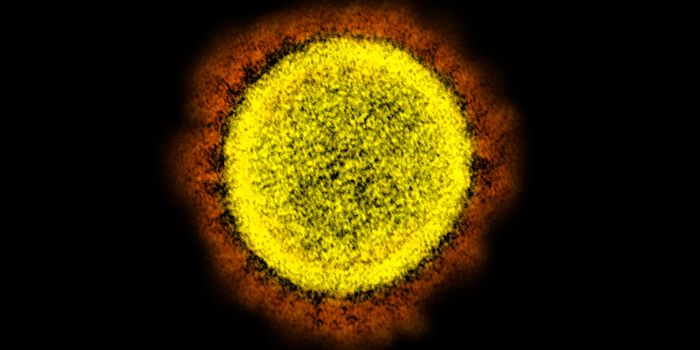

MAR 14, 2022ImmunologyThough it may happen at different rates for different microbes, mutations happen, and SARS-CoV-2, the virus that causes ...

NOV 26, 2021MicrobiologyOn Thursday, November 2021, South African health officials announced that they had identified a new variant of the pande ...